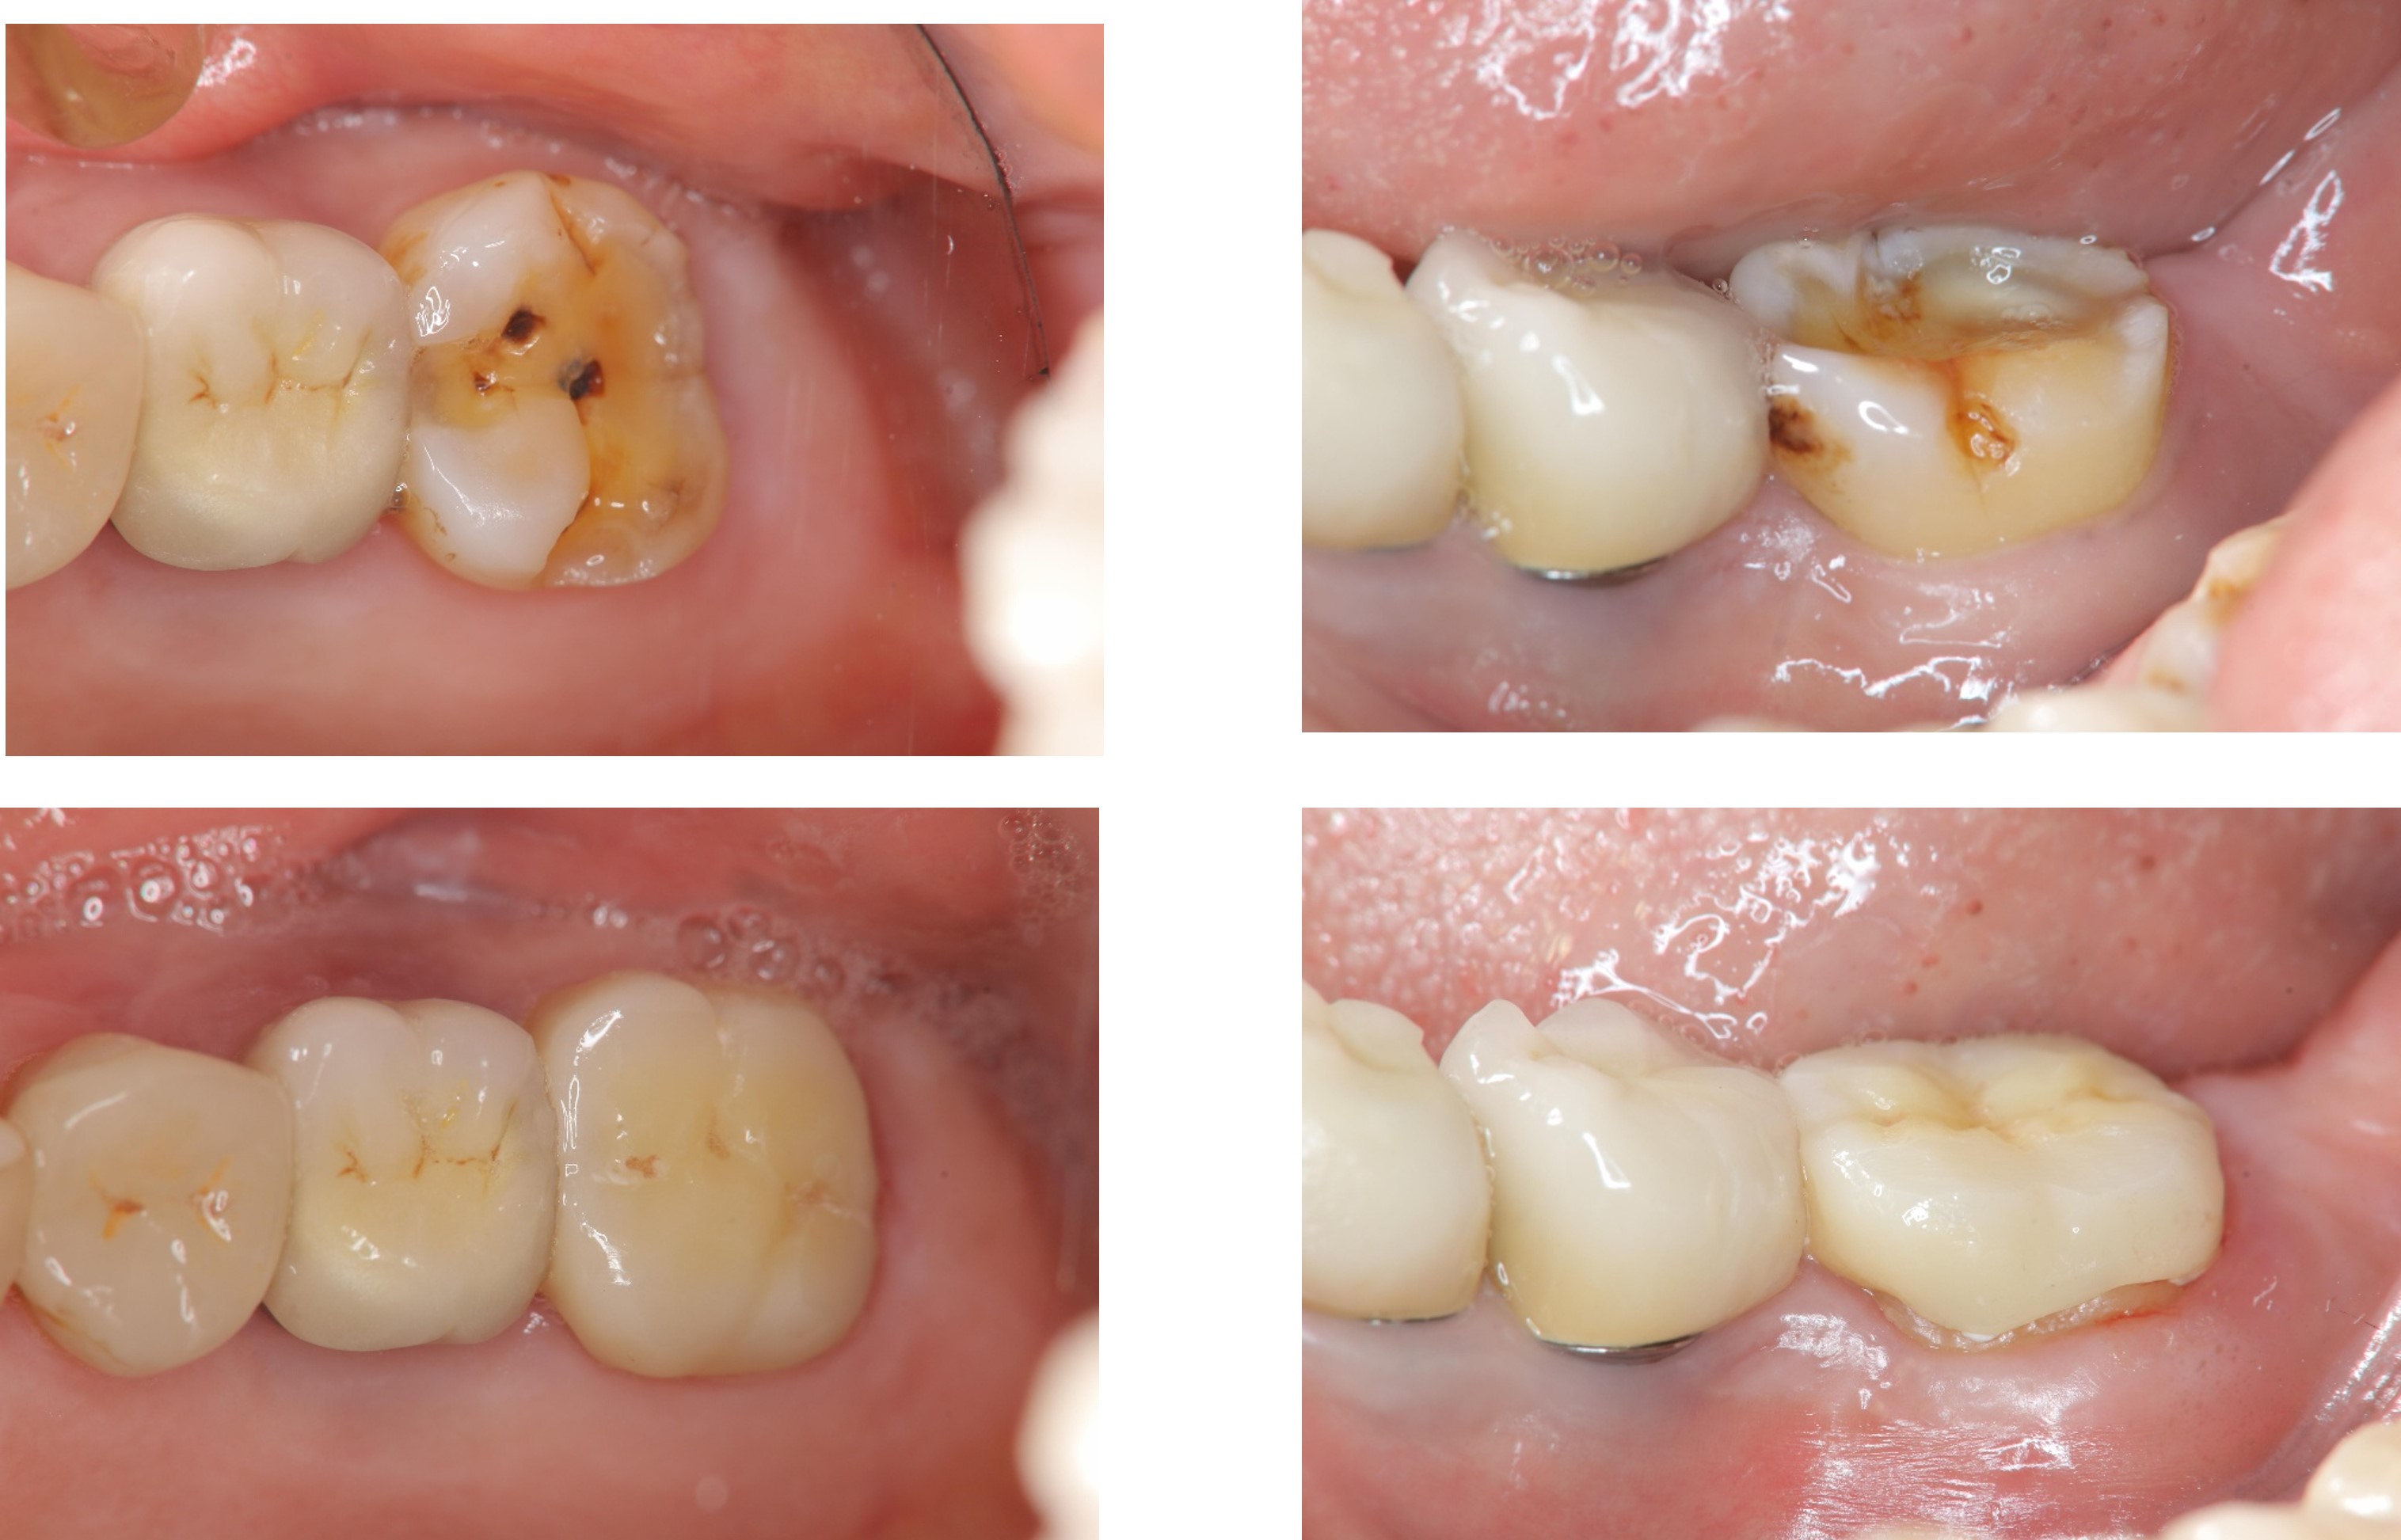

治療前,左上及左下第二大臼齒磨耗

膺復前評估牙齦、牙齒狀態

治療後,牙周咬合良好

治療後,密合度良好

術前、術後比較